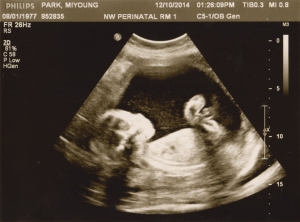

Last Ultrasound